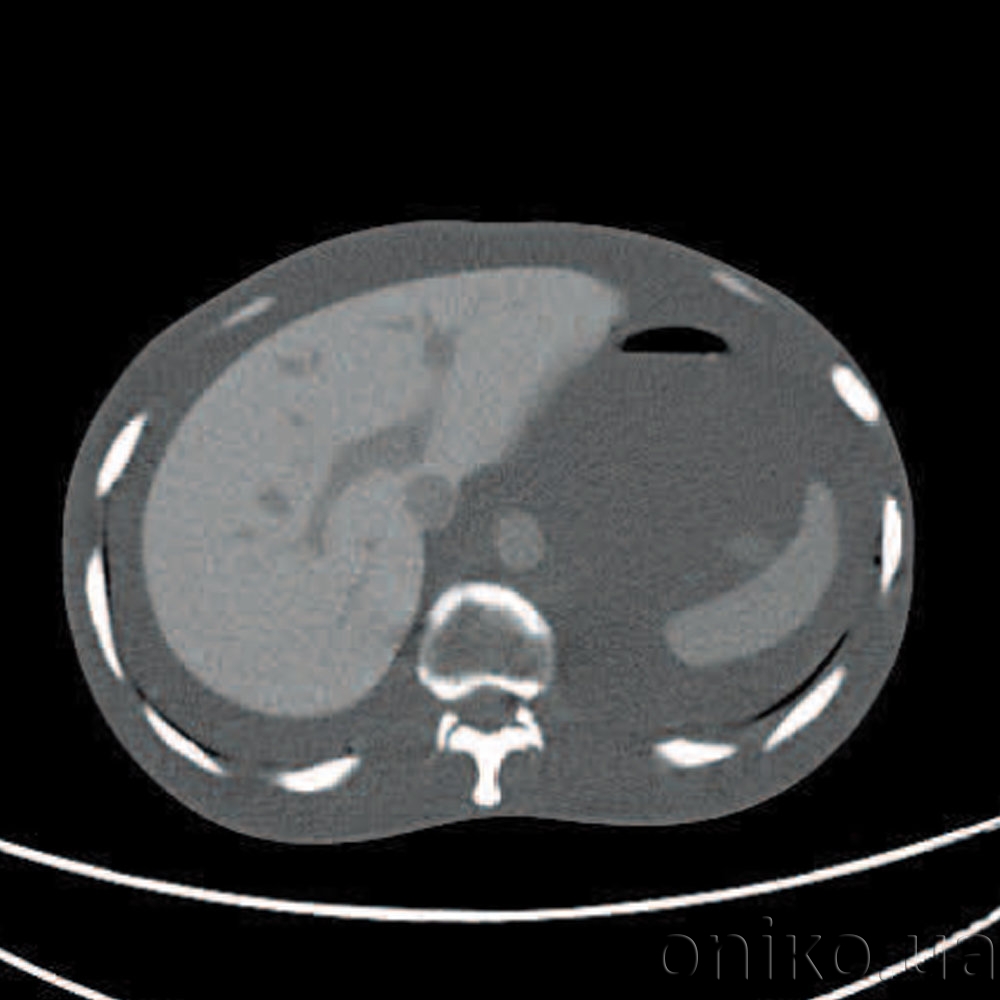

Jednodílný antropomorfní Fantom lidského trupu s anatomickými strukturami umožňuje praktikovat různé techniky počítačové tomografie, včetně spirálového skenování.

- Celá struktura fantomu pomáhá studovat objemové CT skenování včetně spirály

- Fantom lze použít pro nastavení pro zobrazovací radioterapii